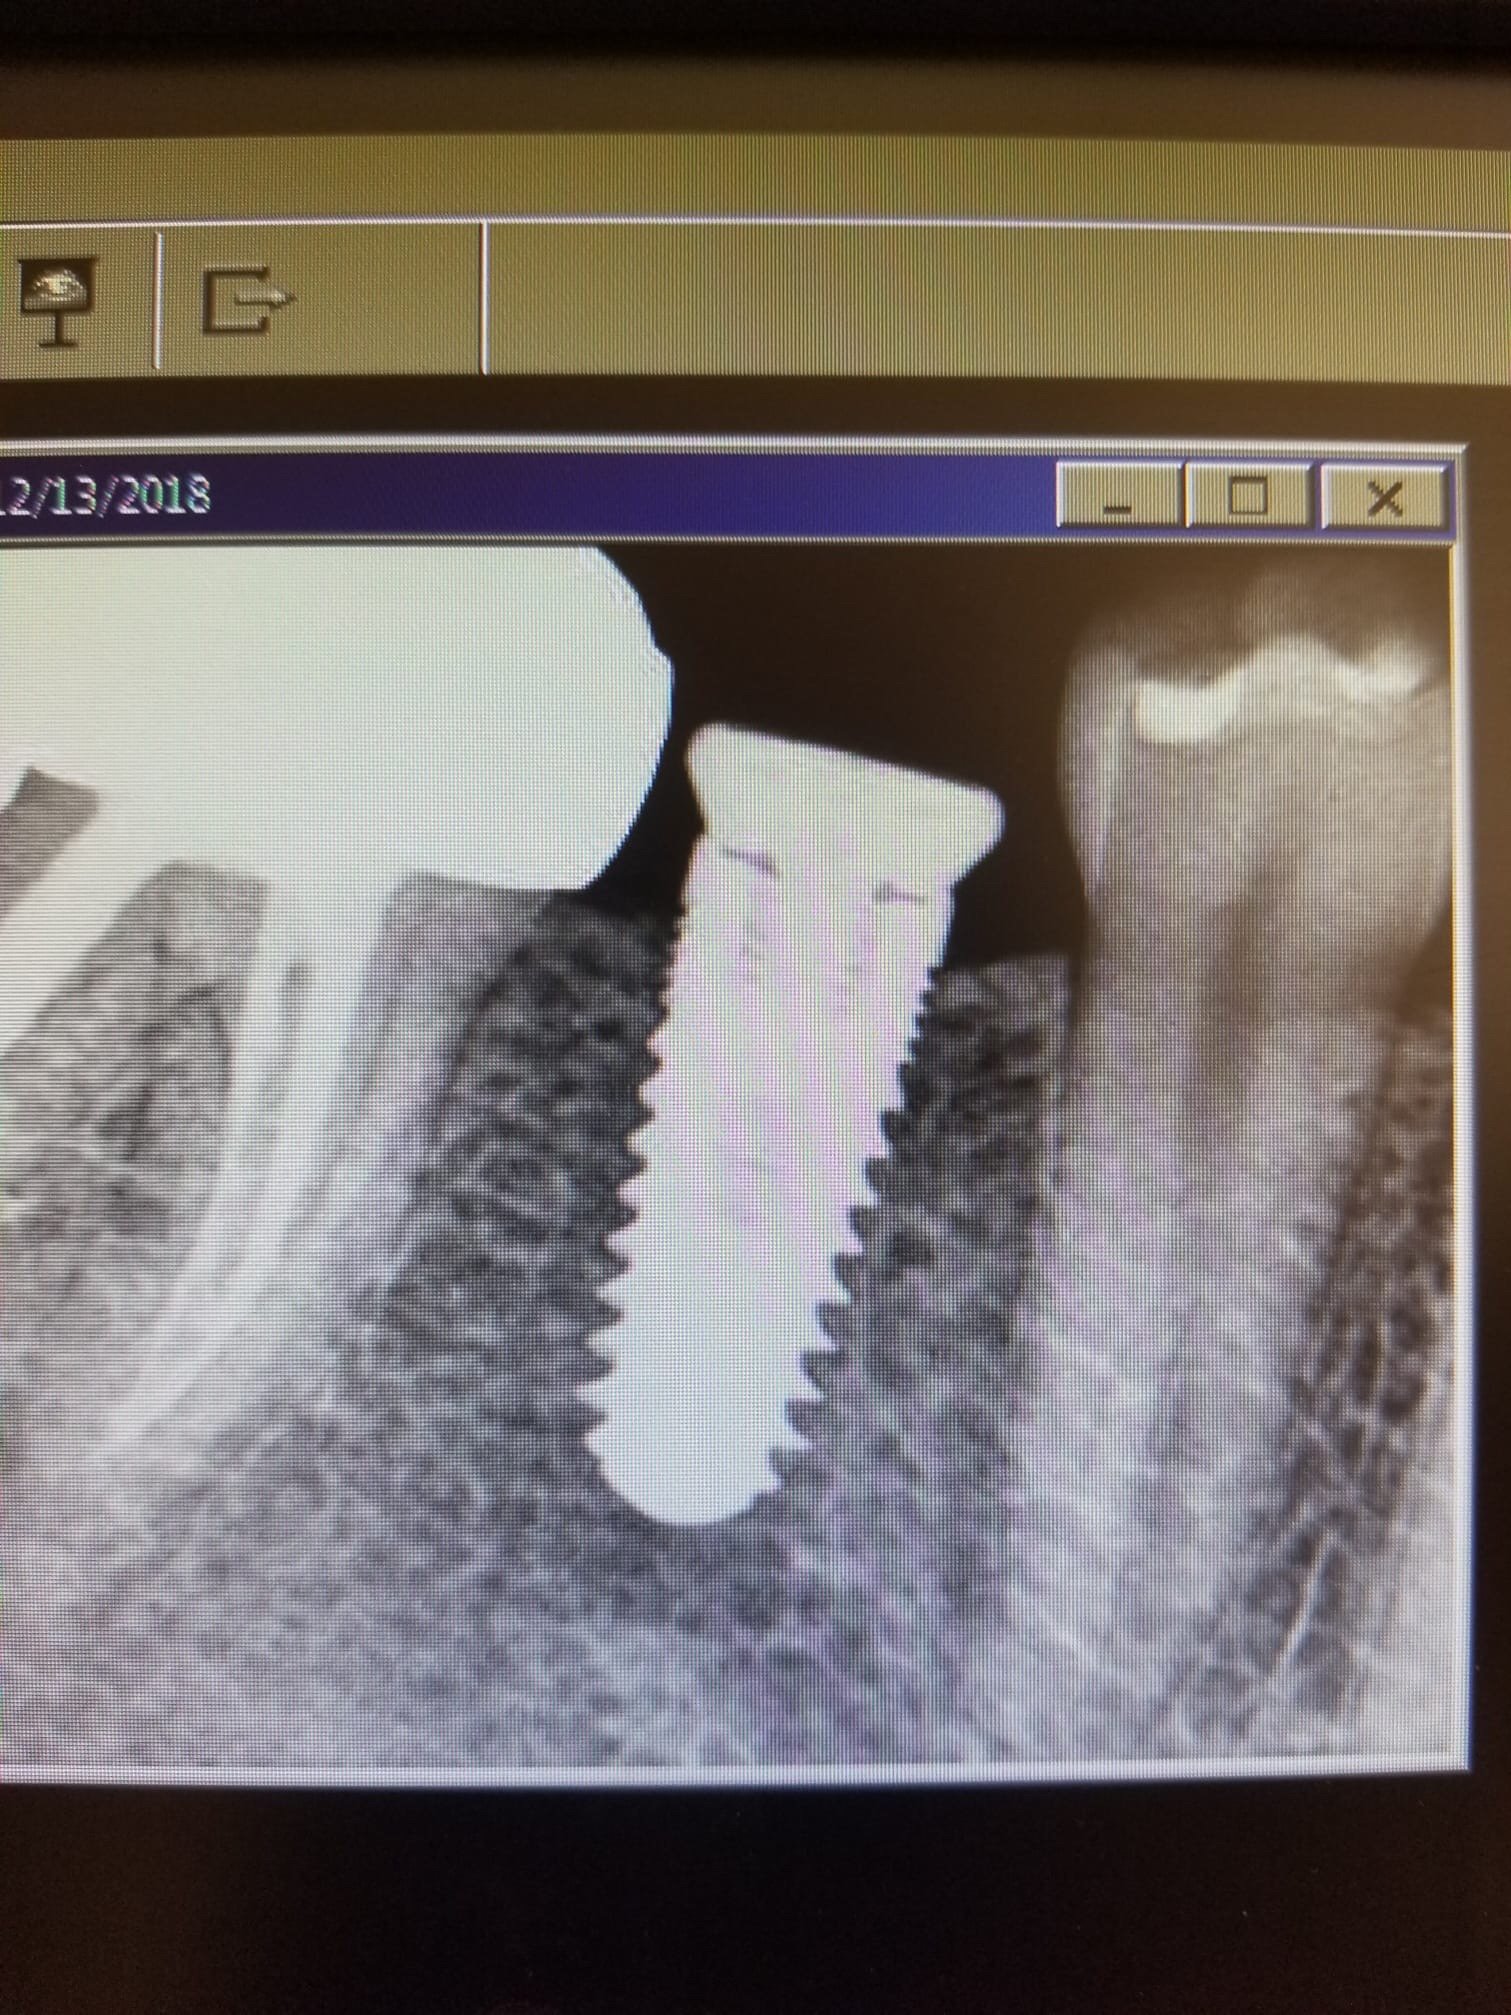

Dental Implant Exposed Threads . With otherwise good implant health, regenerative bone grafting procedures may be the solution for these subgingivally exposed threads. exposed interproximal implant threads after physiologic bone remodeling may be an independent risk indicator for incident peri. an unconventional technique was used to address the challenge of exposed dental implant threads. an unconventional technique was used to address the challenge of exposed dental implant threads. i placed an implant in the maxillary right second premolar region 6 months prior. Implant exposure due to faulty placement, posses as the most common reason for implant failure.

an unconventional technique was used to address the challenge of exposed dental implant threads. i placed an implant in the maxillary right second premolar region 6 months prior. an unconventional technique was used to address the challenge of exposed dental implant threads. exposed interproximal implant threads after physiologic bone remodeling may be an independent risk indicator for incident peri. Implant exposure due to faulty placement, posses as the most common reason for implant failure. With otherwise good implant health, regenerative bone grafting procedures may be the solution for these subgingivally exposed threads.

Dental Implant Too Shallow Complication…Not Deep Enough Ramsey Amin, DDS Dental Implant Exposed Threads Implant exposure due to faulty placement, posses as the most common reason for implant failure. With otherwise good implant health, regenerative bone grafting procedures may be the solution for these subgingivally exposed threads. exposed interproximal implant threads after physiologic bone remodeling may be an independent risk indicator for incident peri. an unconventional technique was used to address the. Dental Implant Exposed Threads.